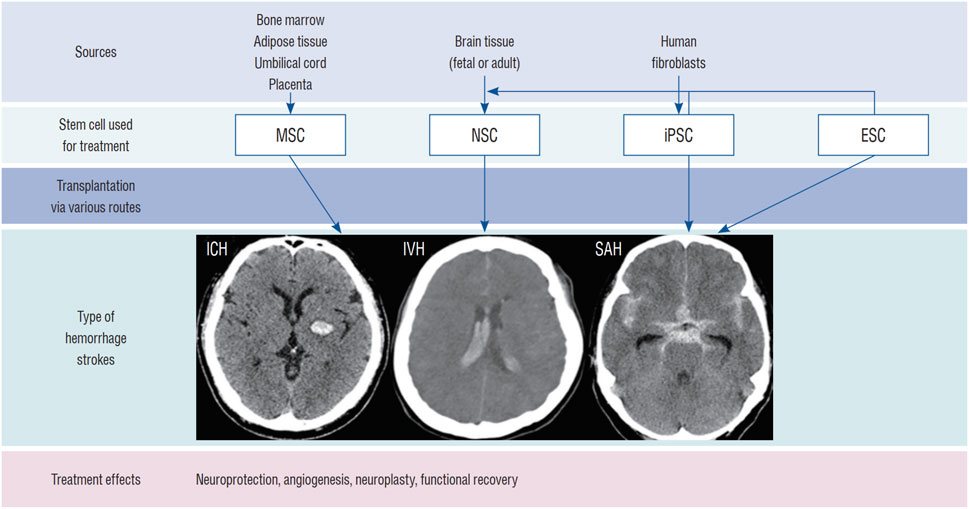

綜述結果表明,神經干細胞治療ICH的機制涵蓋替代神經元、免疫調節與促進血管生成等多重途徑;其來源可分為內源性激活與外源性移植,后者包括原代培養、多能干細胞分化及體細胞重編程;輸送途徑主要有立體定向腦內注射、經腦脊液移植及血管內注射,各有優劣。

目前,神經干細胞移植主要通過腦內移植、鞘內/腦室內注射(經腦脊液途徑)、血管內注射和鼻內給藥等途徑進行。最常用的方法是直接腦內移植。然而,每種方法都有其獨特的優缺點,目前尚未確定統一的移植途徑(圖1)。

包括鼻內給藥,該方法利用嗅神經通路,可無創地將細胞遞送至腦內,最大限度地減少繼發性損傷。例如,Sun等人在動物模型中發現,鼻內給予缺氧預處理的間充質干細胞后,能在腦出血腦組織中檢測到這些細胞。此外,腹腔注射以及結合生物材料或納米技術的聯合給藥途徑,也在探索中,旨在進一步提高移植細胞的存活、滯留和靶向效率(圖1)。